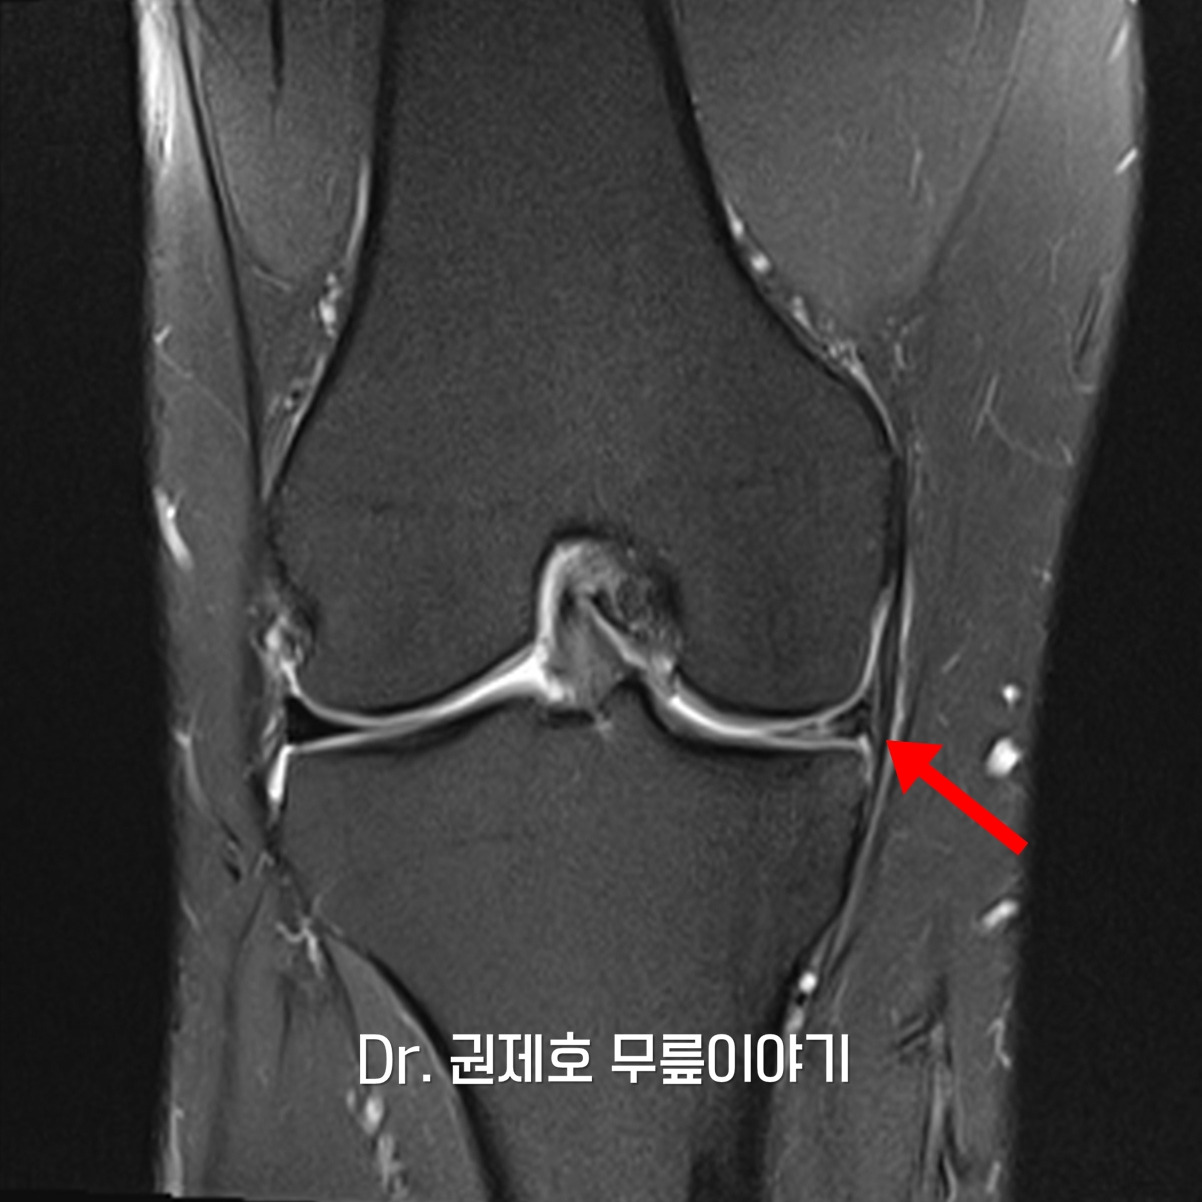

무릎 MRI 검사를 통해 무릎 속에 구조물들 중에서 어떤 것에 문제가 있는지 확인하게 되는데, 검사 결과 무릎연골판이 방사형파열이 있음을 확인하였다.